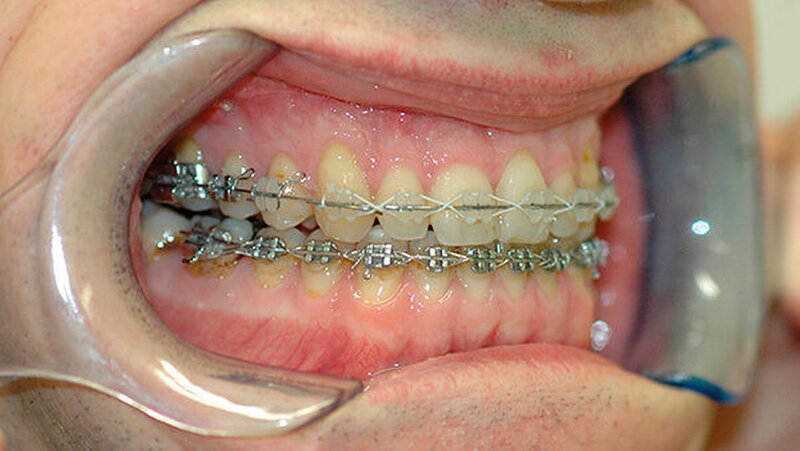

Das deutlich harmonischeres Profil drei Monate nach der Operation: Im Mai des nachfolgenden Jahres wurden die Metallplatten in einem ambulanten Eingriff wieder entfernt. Eine Multibandapparatur hält die Zähne noch "in der Reihe". Der Patient kann heute dank der individuellen innovativen Behandlung ein normales Leben führen, die Gesichtsästhetik und seine Kaufunktion sind vollständig wiederhergestellt.

Mit einer Säge wurde ein gezielter Knochenschnitt durchgeführt. Nach der Präparation wurde der zahntragende Abschnitt des Oberkiefers vom restlichen Gesichtsschädel gelöst. Erst wurde die Bisssituation anhand des Bissschlüssels exakt eingestellt, dann mit 2 mm dicken Osteosyntheseplatten aus Titan der Knochen in der neuen Position mithilfe von Titanschrauben fixiert.

Die neue Position wurde mit einem zweiten Bissschlüssel, der die endgültige Bisssituation einstellt,zugeordnet und mit Osteosyntheseplatten und -schrauben gesichert. Die Operation ging mit einem stationären Aufenthalt von nur fünf Tagen einher.